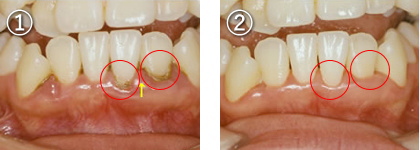

1.歯肉に腫れ、歯と歯肉の境目に多量の歯石が見られます

2.歯石を除去し、正しいブラッシングを行う事で歯肉の腫れも改善しました